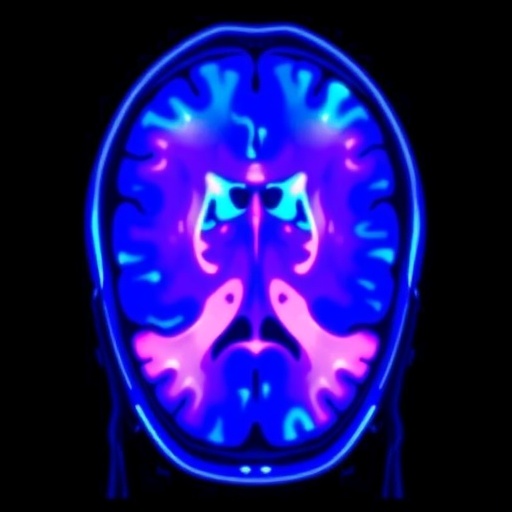

In a remarkable stride forward in the realm of medical imaging, researchers at the University of Birmingham have unveiled a revolutionary class of MRI contrast agents that promise to substantially enhance both the efficacy and safety of magnetic resonance imaging. This advancement emerges from their innovative approach centered on chemical cross-linking, which significantly stabilizes synthetic protein-like structures termed metallo coiled coils. These structures are instrumental in binding gadolinium, a heavy metal element widely used in MRI contrast agents, renowned for its paramagnetic properties that facilitate clearer and more detailed imaging of internal tissues.

This novel approach not only enhances the physical robustness of the contrast agents but also yields a marked improvement in their MRI relaxivity — a measure of their ability to enhance image contrast at clinically relevant magnetic fields. The research demonstrated an impressive 30% increase in relaxivity when comparing cross-linked metallo coiled coil agents with their non-cross-linked counterparts. Such an increase translates directly into clearer and sharper imaging capabilities, potentially allowing for reduced gadolinium dosages and minimizing patient exposure to the metal.

Gadolinium-based contrast agents are a cornerstone of modern MRI diagnostics due to their unparalleled ability to enhance the visibility of vascular structures and pathological tissues. However, concerns persist regarding gadolinium retention in bodily tissues and the consequent toxicity risks, emphasizing the need for safer, more stable molecular carriers. The covalent cross-linking technique, as developed in this study, effectively minimizes the dissociation and potential release of gadolinium ions, thereby improving the safety profile of these agents while maintaining or even enhancing their imaging performance.